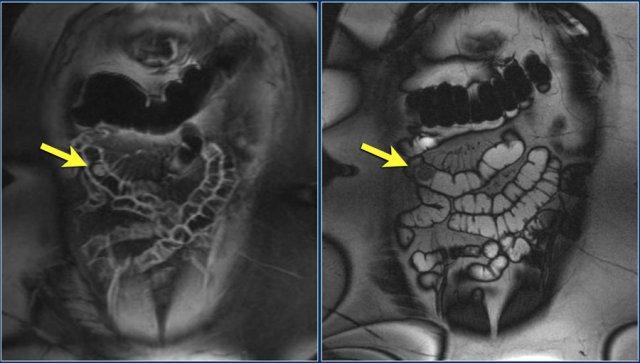

Chuỗi xung T1W sau tiêm thuốc tương phản từ có fat-sat (trái) và chuỗi xung T2W (phải) cho thấy một khối gây tắc nghẽn ở hỗng tràng với bờ dạng vai (mũi tên).

Có giãn ruột trước chỗ hẹp.

Đây là ung thư biểu mô tuyến ở đoạn gần hỗng tràng.

Khối u được hiển thị rõ hơn trên MRI so với CT.